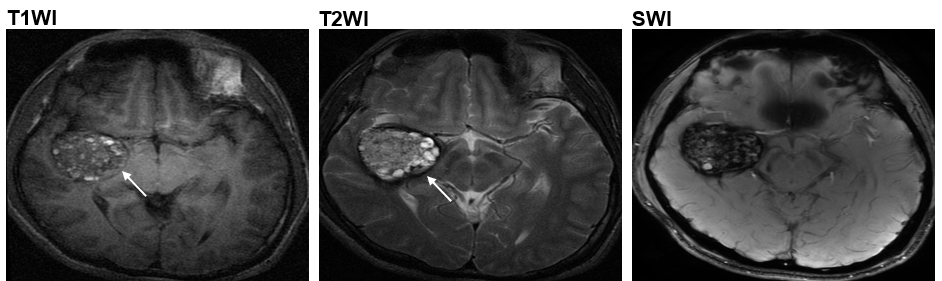

如今,由生命科學部兼化學及生物工程學系助理教授王吉光以及北京天壇醫院曹勇教授帶領的研究團隊,分析了113名CCM患者的基因組數據後,發現於四種CCM患者當中,幾乎所有於腦血管中長有爆谷形狀腫瘤,亦即四種CCM患者中屬最為普遍的二型1的患者,均出現一個名為「MAP3K3 c.1323C>G」基因突變。

現時,磁力共振成像(MRI)是一種醫生常用於診斷CCM的「非入侵性」方法。然而,MRI只能讓醫生知道血管瘤的大小及類別;至於是哪一個基因突變導致CCM,醫生一般則只能透過手術以及化驗得知。不過,科大研究團隊設計了一個電腦程式,可以評估MRI 影像所顯示的血管瘤與MAP3K3 c.1323C>G基因突變關係的概然率。因此,病人毋須「開刀」便得知是否存在MAP3K3 c.1323C>G基因突變,不但能減低施手術可能帶來的腦出血或腦神經功能缺損等風險,亦可令病者及早展開更針對性的治療。